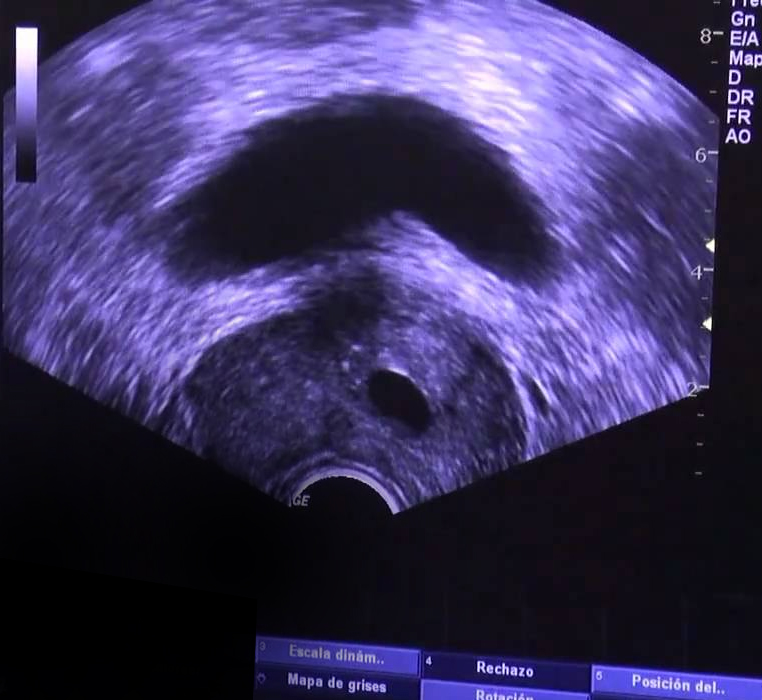

Ecografía Prostática Transrectal